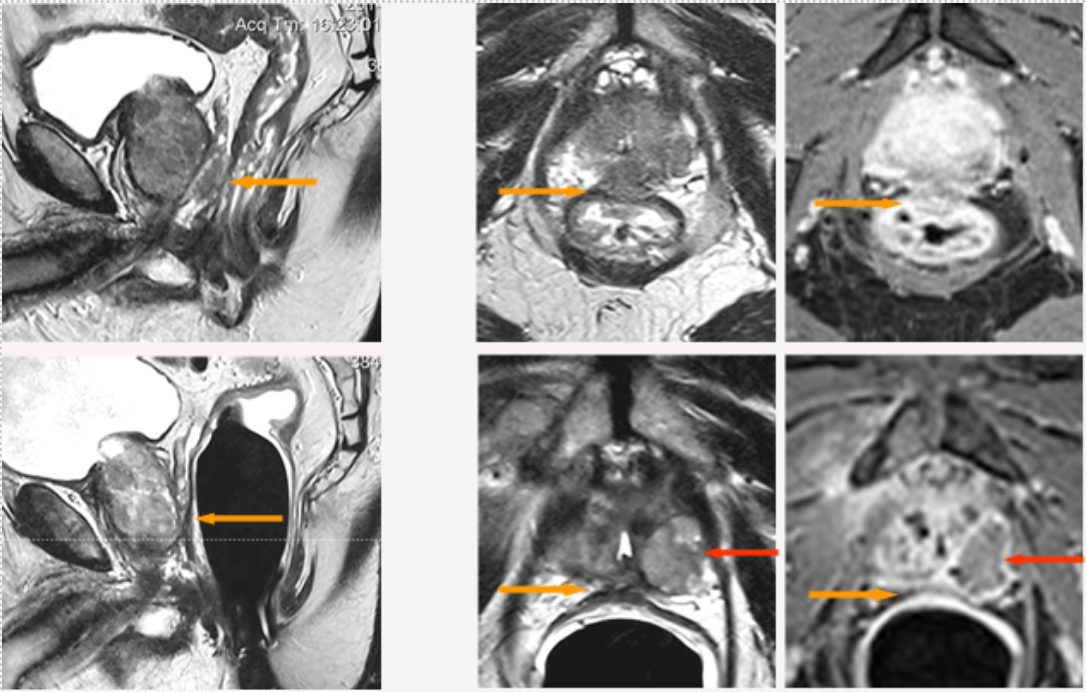

Abbildung 3 zeigt die Behandlung eines Prostatakarzinoms Stadium T4, N0, M0, Gleason-Score 8, bei einem 79-jährigen Mann mit Infiltration des Enddarmes (Rektums; gelbe Pfeile oben). Eine radikale Prostatektomie wäre nur mit zusätzlicher Entfernung des Rektums und Anlage eines künstlichen Darmausganges (Anus praeter) möglich gewesen.

Die Infiltration des Enddarmes ist auf den MRT-Bildern in der oberen Reihe der Abbildung Z abgebildet: Links: seitliche (sagittale) Aufnahme; Mitte: Querschnitt (axiale Aufnahme) mit T2-Wichtung; Rechts: Querschnitt (axiale Aufnahme) nach Kontrastmittelgabe.

Die untere Bildreihe zeigt die Verhältnisse 9 Monate nach der IRE-Behandlung: Die Wand des Enddarmes stellt sich normal, ohne Verletzung und ohne Fistel (Fehlverbindung) zur Prostata dar: Links: seitliche (sagittale) Aufnahme; Mitte: Querschnitt (axiale Aufnahme) mit T2-Wichtung; Rechts: Querschnitt (axiale Aufnahme) nach Kontrastmittelgabe.